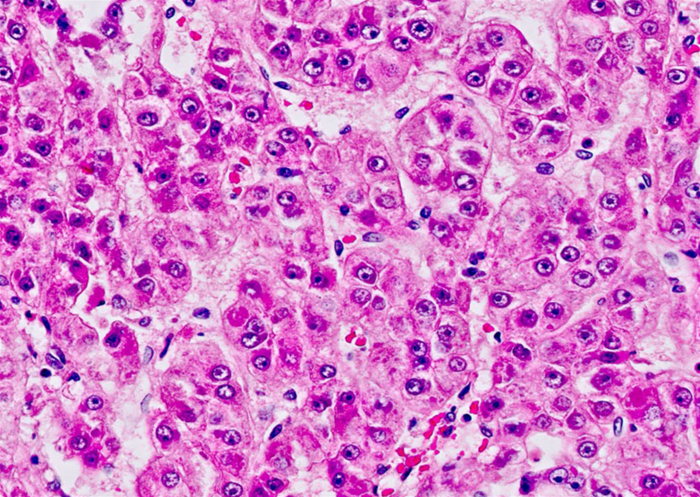

A 58-year-old man with a history of chronic liver disease secondary to hepatitis C infection comes to the office due to progressive fatigue and abdominal discomfort.  He has no other medical conditions, and a recent colonoscopy was normal.  Physical examination shows ascites and jaundice.  Ultrasonography of the abdomen reveals a solid mass within the liver parenchyma.  Surgical resection of the liver lesion is performed.  Microscopy reveals large cells with prominent nucleoli arranged in thickened plates as shown below. A 58-year-old man with a history of chronic liver disease secondary to hepatitis C infection comes to the office due to progressive fatigue and abdominal discomfort.  He has no other medical conditions, and a recent colonoscopy was normal.  Physical examination shows ascites and jaundice.  Ultrasonography of the abdomen reveals a solid mass within the liver parenchyma.  Surgical resection of the liver lesion is performed.  Microscopy reveals large cells with prominent nucleoli arranged in thickened plates as shown below.   Which of the following serum markers would be most useful for monitoring this patient for disease recurrence? A) 5-Hydroxyindoleacetic acid B) Alpha-fetoprotein C) CA 125 D) CA 19-9 E) Carcinoembryonic antigen F) Human chorionic gonadotropin Which of the following serum markers would be most useful for monitoring this patient for disease recurrence?